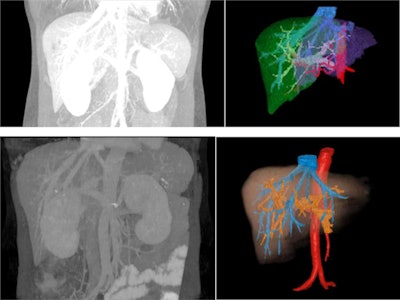

The team assessed the utility of 3D VR and MIP for anatomic delineation of hepatic vascularity. Contrast-enhanced abdominal CT images from patients with malignancies involving the liver who were undergoing surgical evaluation at the City of Hope Helford Hospital between 2009 and 2015 were initially reviewed by experienced academic radiologists.

All initial images had been obtained as part of routine care. Of the studies from 128 patients, only 38 were done with multiphase protocols including both arterial and venous phases. Images were reconstructed into 0.625 x 1.25-mm slices for postprocessing and uploaded to General Electric Advanced Workstation Server 3.2 for analysis. 3D MIP images were generated by merging arterial and venous phase images with a "drag and drop" tool.

2D images were registered using nonrigid automatic registration. Studies with limited MIP clarity due to motion artifact and suboptimal contrast enhancement were excluded from further analysis. The Volume Computer Assisted Reading (VCAR) software was used to generate scaled 3D images of the 13 studies that had suitable MIP images.

3D color-enhanced volume rendering was performed using the CT arterial and venous phase images. The images were imported in to GE AW workstation, and quantitative volumetric assessment was performed using the automatic hepatic VCAR tool with manual edits when needed. The hepatic artery, hepatic vein, and portal vein were extracted manually based on Hounsfield unit thresholds and were colored individually. Liver lobes were segmented using the virtual scalpel, and color enhancement was applied.

Overall, color enhancement could only be applied with 3D VR imaging and not MIP imaging. Volume calculation and isolation of liver segments were also possible with 3D VR but not MIP imaging. Image rotation in the superior to inferior, the anterior to posterior, and the lateral view was achieved with both modalities. Vessel delineation was better visualized with 3D VR imaging. The clarity of individual small vessels was suitable with both modalities. The overall performance indicates that 3D VR is the superior methodology to delineate the anatomical features, compared with the MIP.